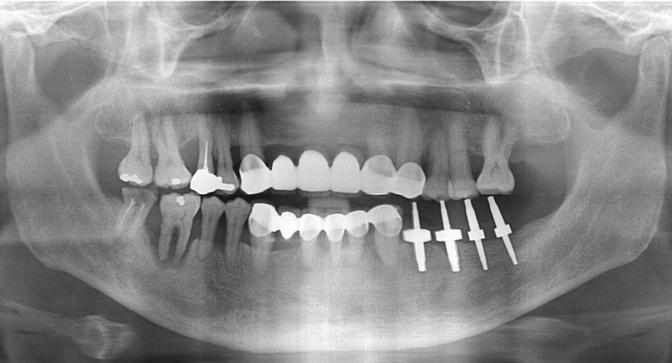

SRT

| implant model | SRT |

|---|---|

| surgery date | 2012.11.09 |

| gender | Male |

| age | 55 |